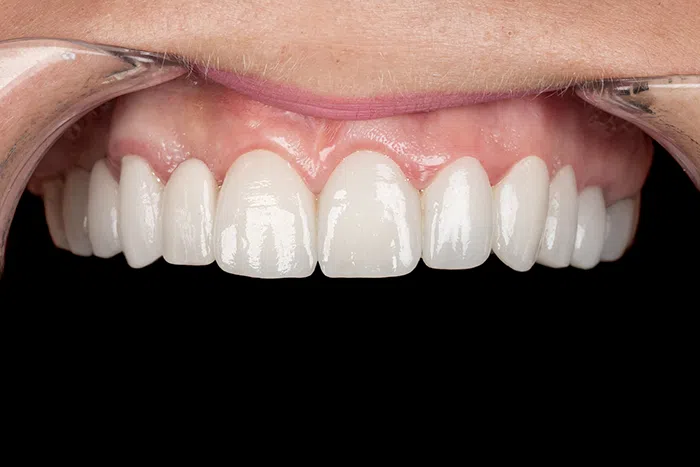

Caz de estetică dentară – Fațete ceramică presată E-Max

Provocarea acestui caz a fost în prepararea minim invazivă a dinților centrali rotați și a obține o formă și o culoare cât mai naturală, pacienta dorind un caz de estetică dentară ce să nu fie observabil.

Pacienta a beneficiat de corecție gingivala cu laser pentru uniformizarea asimetriilor gingivale, tratamente endodontice de canal sub microscop, obturațiile vechi (plombe) schimbate cu materiale de compozit cu particule nanoceramice, și fațete dentare din ceramică presată E-Max.

Termen de finalizare 2 săptămâni de la amprentarea finală.